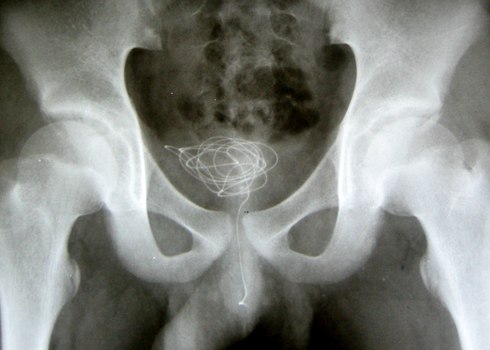

| Sợi dây điện nằm trong bàng quang của bệnh nhân. |

Các bác sĩ Bệnh viện Nhi Đồng 2, TP HCM vừa lấy ra một sợi dây điện còn nguyên vỏ và lõi dài gần một mét từ lỗ tiểu của bệnh nhân nam 15 tuổi. Dị vật nằm gọn trong bàng quang đã có dấu hiệu nhiễm trùng.

Nhập viện trong tình trạng đau vùng bụng dưới, bệnh nhân cho biết đã nghịch nhét dây điện vào lỗ tiểu, hai ngày sau đó do bị đau nên khai với người lớn. "Em thấy thích thích nhưng sau đó thì thấy đau", bệnh nhân cho các bác sĩ biết.